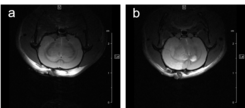

For studying disease pattern of stroke patients, we use a rat animal model with induction of focal cerebral ischemia and follow-up by MRI, Fig.7.

Fig. 7: Infarcted rat brain MRI. For comparison of infarct size of induced infarct right after OP and 24 h later a T2 weighted Spinecho sequence was used: repetition time: 3800 ms, echo time: 18.0 ms, field of view: 35x35 mm2, matrix:512x256 and slice thickness 1.0 mm was used to acquire 12 axial slices.